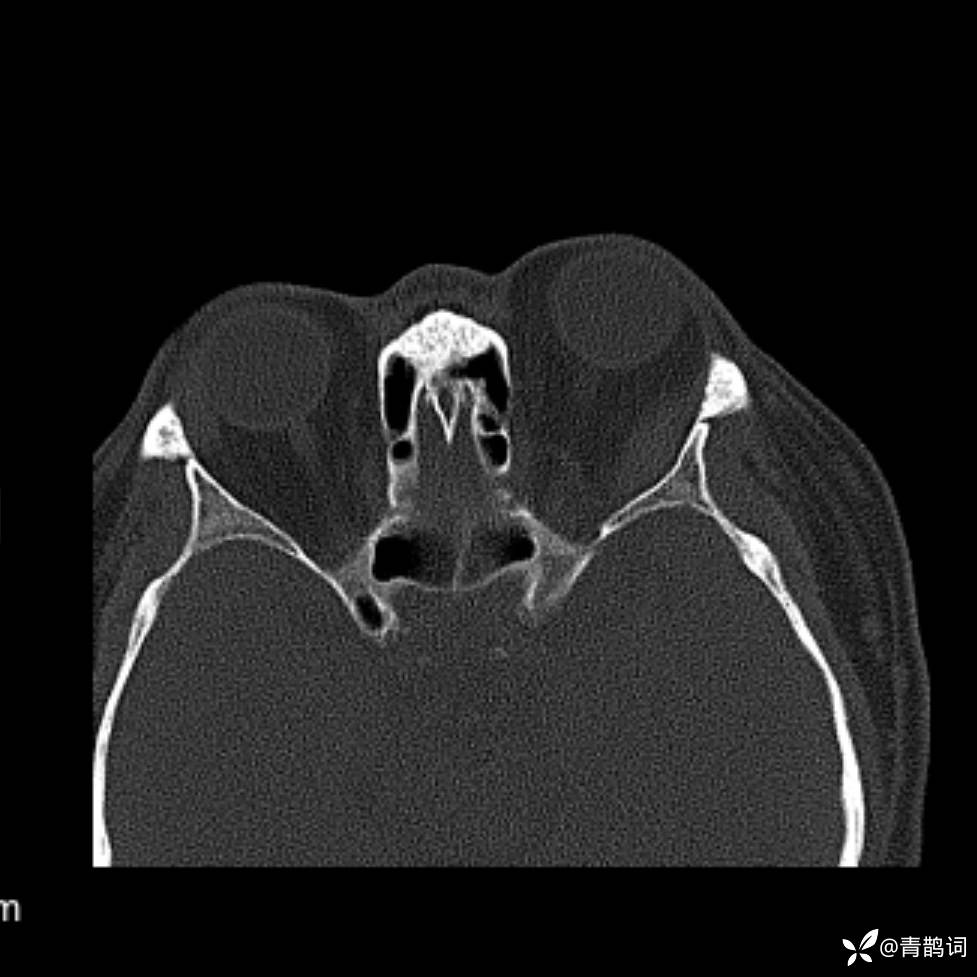

患者年龄:30岁。

患者性别:男。

简要病史:左颜面部肿胀2年,反复咳嗽咳痰,逐渐加重。

结合病史及影像学表现,期待评论区各位老师各抒己见~